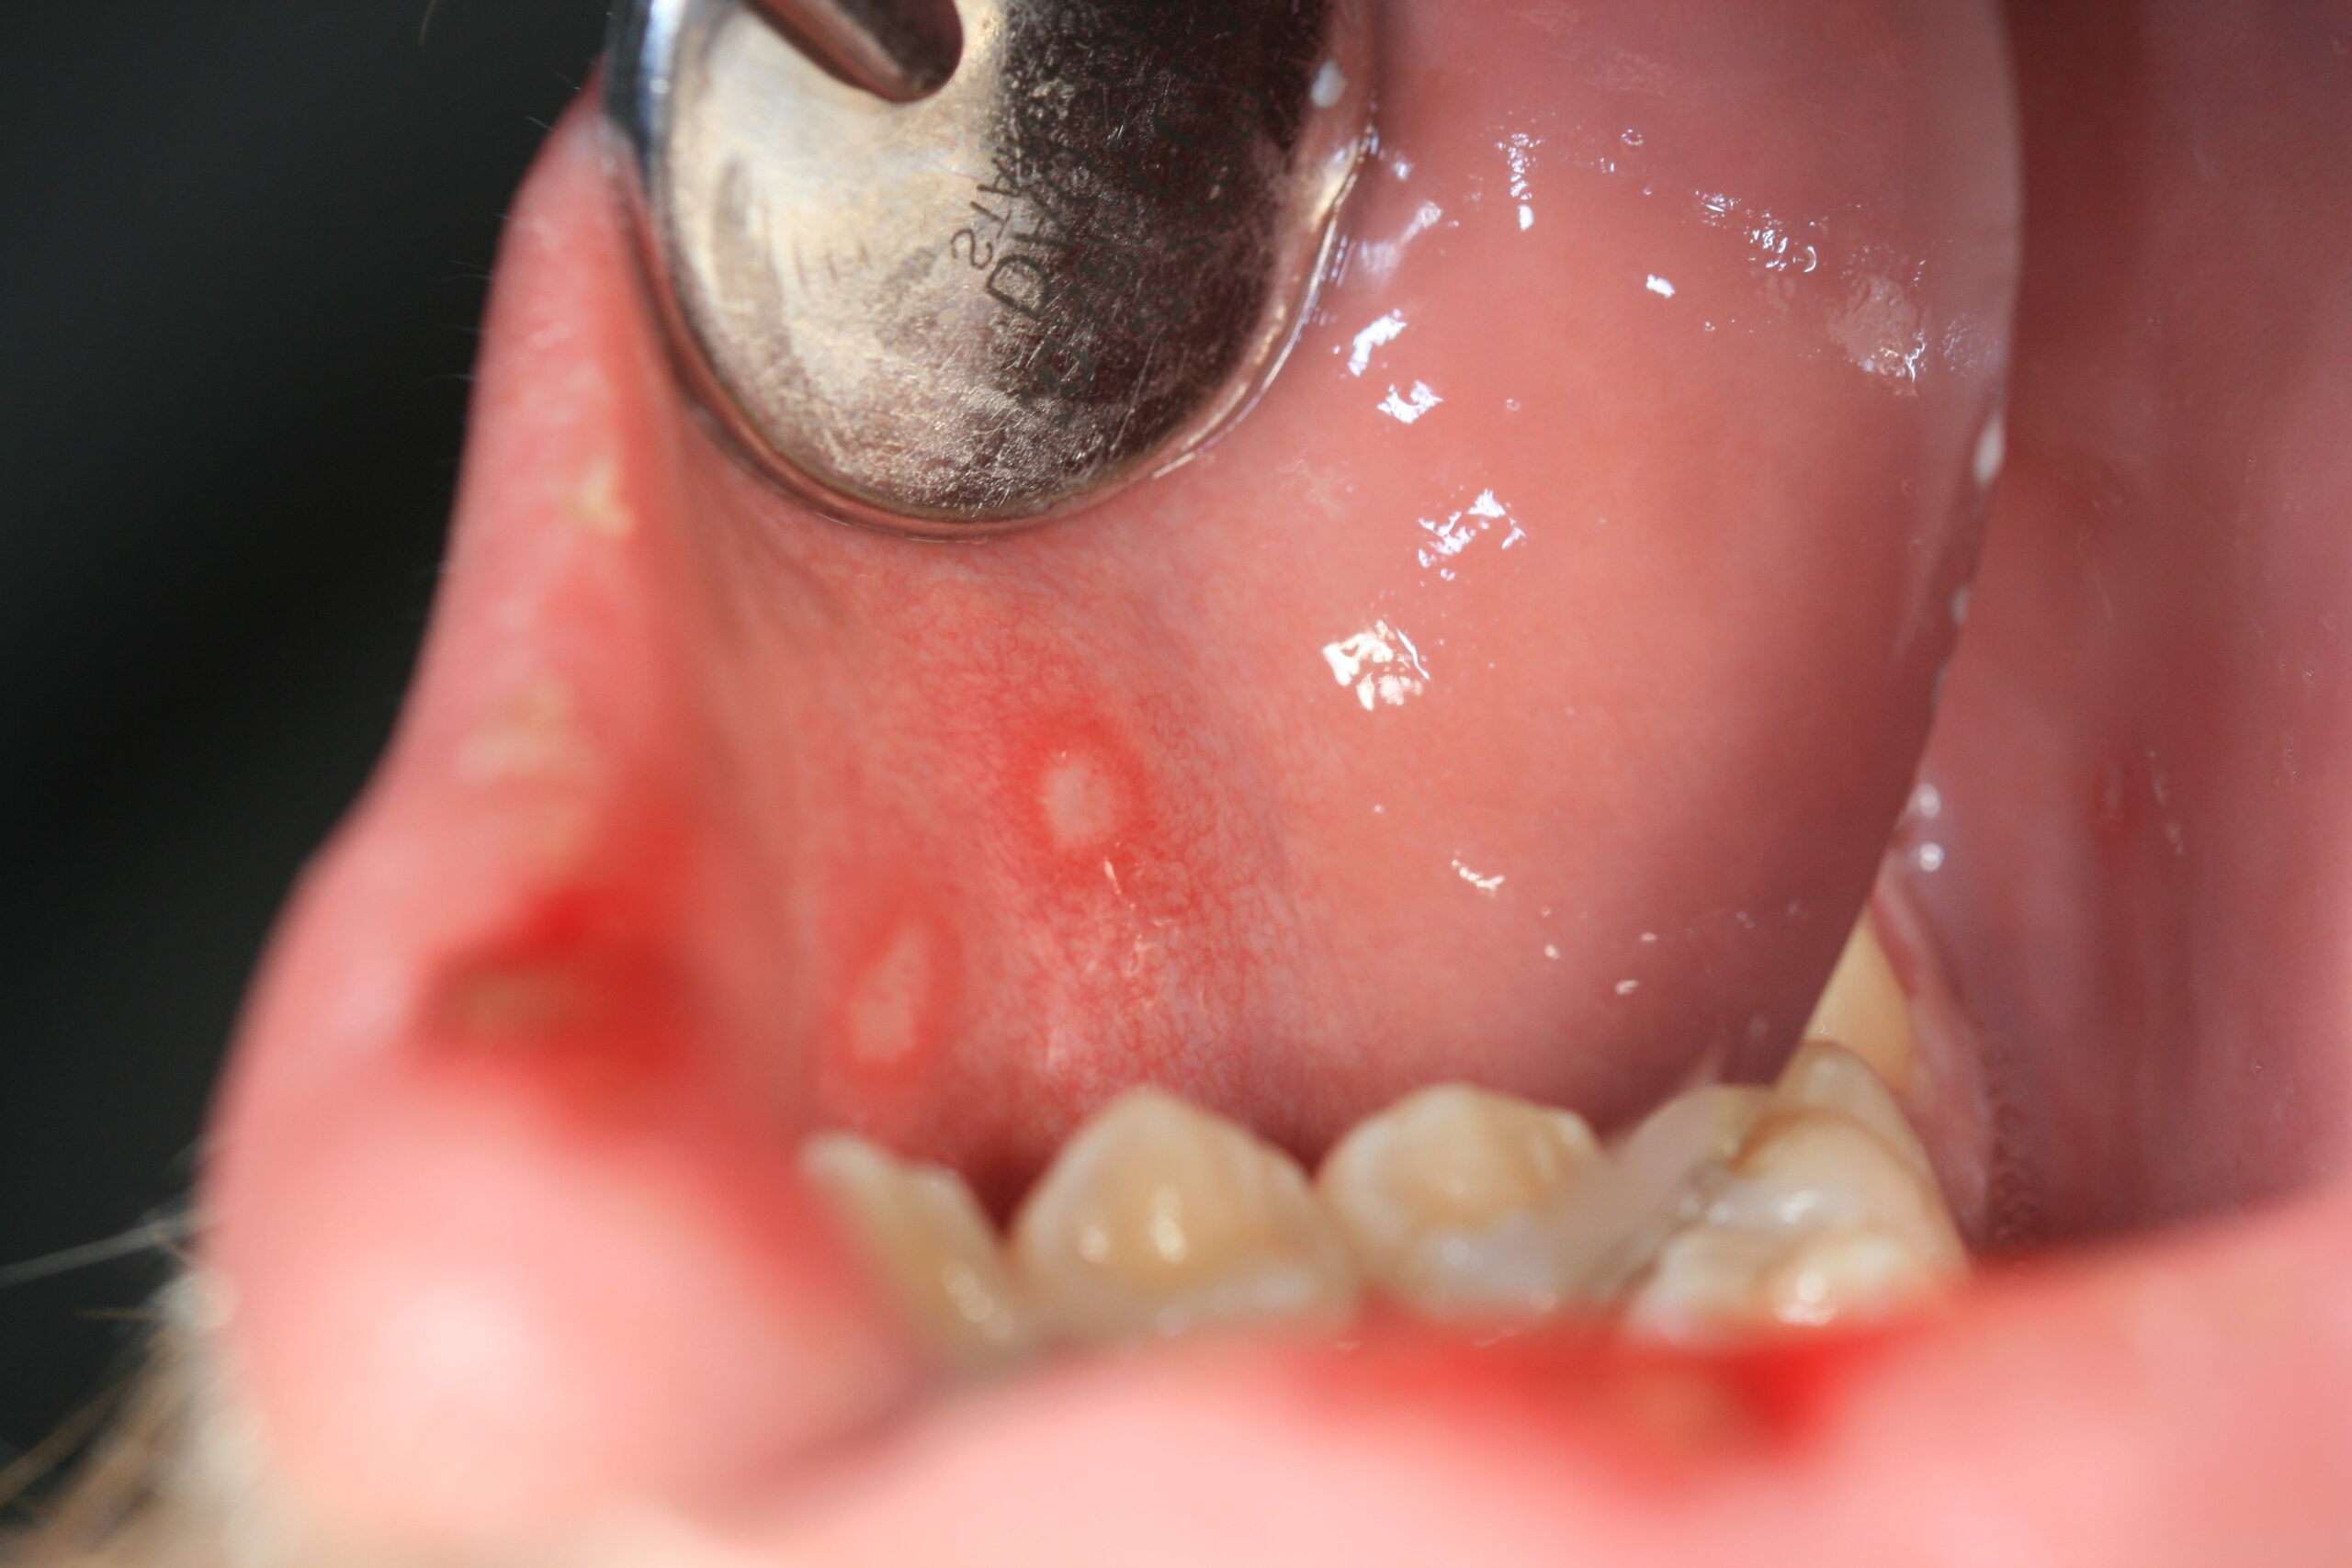

Die Zahnfleisch- und Schleimhautentzündung ist das häufigste Krankheitsbild unter der eine mit Herpes-simplex-Virus 1 erstmalig in Erscheinung tritt. Es zeigen sich viele zerstreut-verteilte Bläschen an der Mundschleimhaut, die sich in runde bis ovale, schmierig belegte Herpes-Aphten umwandeln, die sich aus den Bläschen gemeinsam entwickeln und eine erhebliche Größe entwickeln können.

Der Herpes labialis ist die bekannteste Form der HSV-Reaktivierung, also als wiederkehrender Lippenherpes, und zeigt sich als typische Herpesbläschen („cold sores“, Fieberbläschen) an der Lippenrotgrenze bis hin zum Nasenbereich, seltener auch in Form von gruppierten Schleimhautgeschwüren des harten Gaumens.